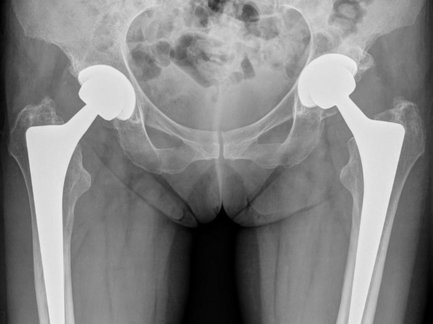

Bei Verschleiß der Hüfte, entsprechendem Leidensdruck und nicht mehr ausreichend ansprechender konservativer Therapie kann die Implantation einer Hüftendoprothese zu einer deutlichen Verbesserung der Lebensqualität führen.

Zum Einsatz kommen moderne zementfreie und zementierte Endoprothesen, die in einer Vielzahl von Registern besonders gute Ergebnisse gezeigt haben. Insbesondere bei jüngeren und aktiven Menschen werden auch Spezialendoprothesen wie die Hüftkappenendoprothesen oder Oberflächenersatzprothesen nach McMinn oder Schenkelhalsprothesen implantiert, um für den Fall einer hoffentlich nie auftretenden Revision genügend Knochenstock zu erhalten. In schwierigen Fällen erfolgt die Implantation mit Navigation. Bei speziellen anatomischen Situationen wird unter Umständen eine individuell für den Patienten angefertigte Endoprothese verwendet.

Hüftendoprothesen werden während eines 8- bis 12-tägigen stationären Aufenthaltes implantiert. Die Operation selbst dauert meistens etwa eine Stunde. Der Eingriff erfolgt in Vollnarkose oder in Rückenmarksanästhesie (Spinalanästhesie). Verschiedene Zugänge sind möglich. Je nach Vor- und Nachteilen werden bei uns anteriore (vordere), anterolaterale (vorne seitliche), seitliche und hintere Zugänge verwendet. Stets achten wir darauf, den Zugang möglichst klein zu halten und insbesondere die Muskulatur zu schonen. Zunächst werden erkrankte Knochen und Knorpel des Gelenkes entfernt, dann wird zunächst eine Hüftgelenkspfanne mit Inlay eingesetzt und schließlich ein Prothesenschaft verklemmt oder einzementiert. Ein aufgesetzter Kugelkopf erlaubt schließlich wieder ein harmonisches Bewegen. Im Regelfall ist der Blutverlust bei diesen Operationen gering, sodass keine Blutkonserven erforderlich werden. Zum Wohl unserer Patienten sammeln wir das Blut schon während der Operation und in den ersten sechs Stunden danach. So können wir es im Bedarfsfall aufarbeiten und retransfundieren. Dies bedeutet, dass wir nur sehr selten Fremdblut einsetzen müssen.

Da auch die Qualität der Endoprothesen für die Haltbarkeit des Endoprothesensystems eine Rolle spielt, verwenden wir nur Qualitätsendoprothesen, die in verschiedensten Studien ihre Standhaftigkeit beweisen konnten. So verwenden wir im Regelfall hochqualitative Implantate der Firma Smith&Nephew, einem Marktführer in Europa, der Schweizer Firma Symbios und der deutschen Firma Link. Die am häufigsten bei uns eingesetzten Modelle sind die Polarstem-Prothese in zementfreier und zementierter Form, die individuelle Hüftendoprothese der Firma Symbios, die McMinn-Hüftkappenprothese, der Link-Revisionsschaft. An Pfannen setzen wir vorwiegend die Epifitpfanne, die R3-Pfanne, die Müller-Flachprofilpfanne ein. Die am häufigsten bei uns verwendete Gleitpaarung ist die Keramik-Keramik-Gleitpaarung oder die Verilast-Technologie mit hochvernetztem Kunststoffinlay und Oxiniumkopf. Hierdurch soll nicht nur die Primärstabilität, sondern insbesondere ein langes Überleben des Endoprothesensystems gefördert werden.